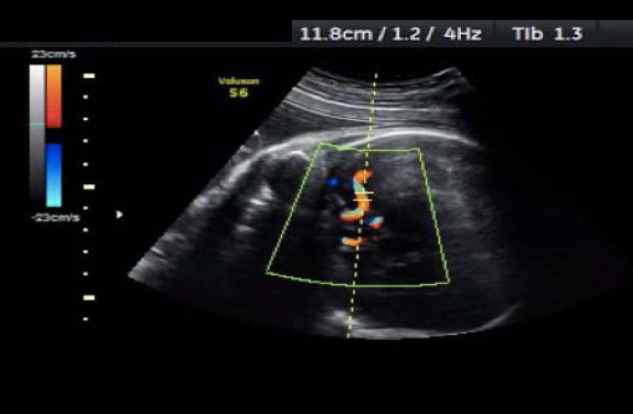

La evaluación de la circulación cerebral fetal (arteria cerebral media) mediante ecografía Doppler puede es la forma ideal para identificar a los bebés con sospecha de anemia y confirmar el diagnóstico con la obtención de una muestra de sangre fetal del cordón umbilical mediante un procedimiento llamado cordocentesis.